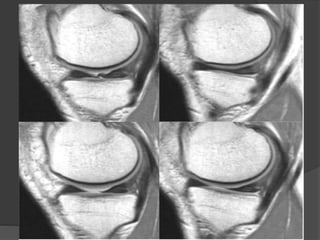

Rx

Cartilago articular

• Rx= imagen indirecta

• RM = buen contraste y visualización

de tejidos circundantes

• RM alta resolución= detecta cambios

morfológicos en el cartílago

RM normal

AXIAL

CORONALES

SAGITAL